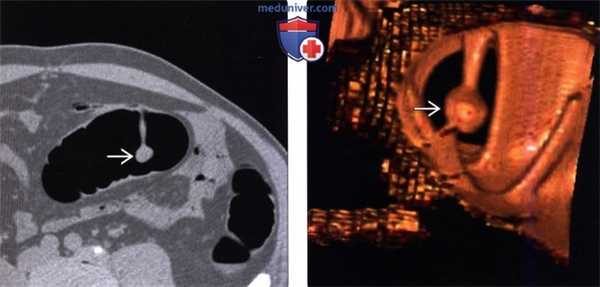

(Слева) На КТ у мужчины 37 лет с ректальным кровотечением и снижением веса тела, практически не идущего на контакт с медицинским персоналом, визуализируются множественные метастазы в печени.

(Справа) На КТ у этого же пациента определяются множественные метастазы в печени, а также небольшое образование в ампуле двенадцатиперстной кишки, которое, как подтвердилось впоследствии, является аденомой. (Слева) На КТ в этом же случае определяется инвагинация тонкой кишки, скорее всего, обусловленная ее полипами (не видны).

(Справа) На КТ у этого же пациента определяется объемное образование в ягодице, имеющее более высокую плотность по сравнению с мышцами, которое, скорее всего, является десмоидной опухолью (фиброматозом). (Слева) На КТ срезе из этого же исследования визуализируется объемное образование в сигмовидной кишке, которое впоследствии было верифицировано как рак.

(Справа) На КТ лицевого скелета, выполненном после КТ органов брюшной полости, определяется утолщение кортикального слоя, видны остеомы. Все эти изменения являются типичными признаками синдрома Гарднера.